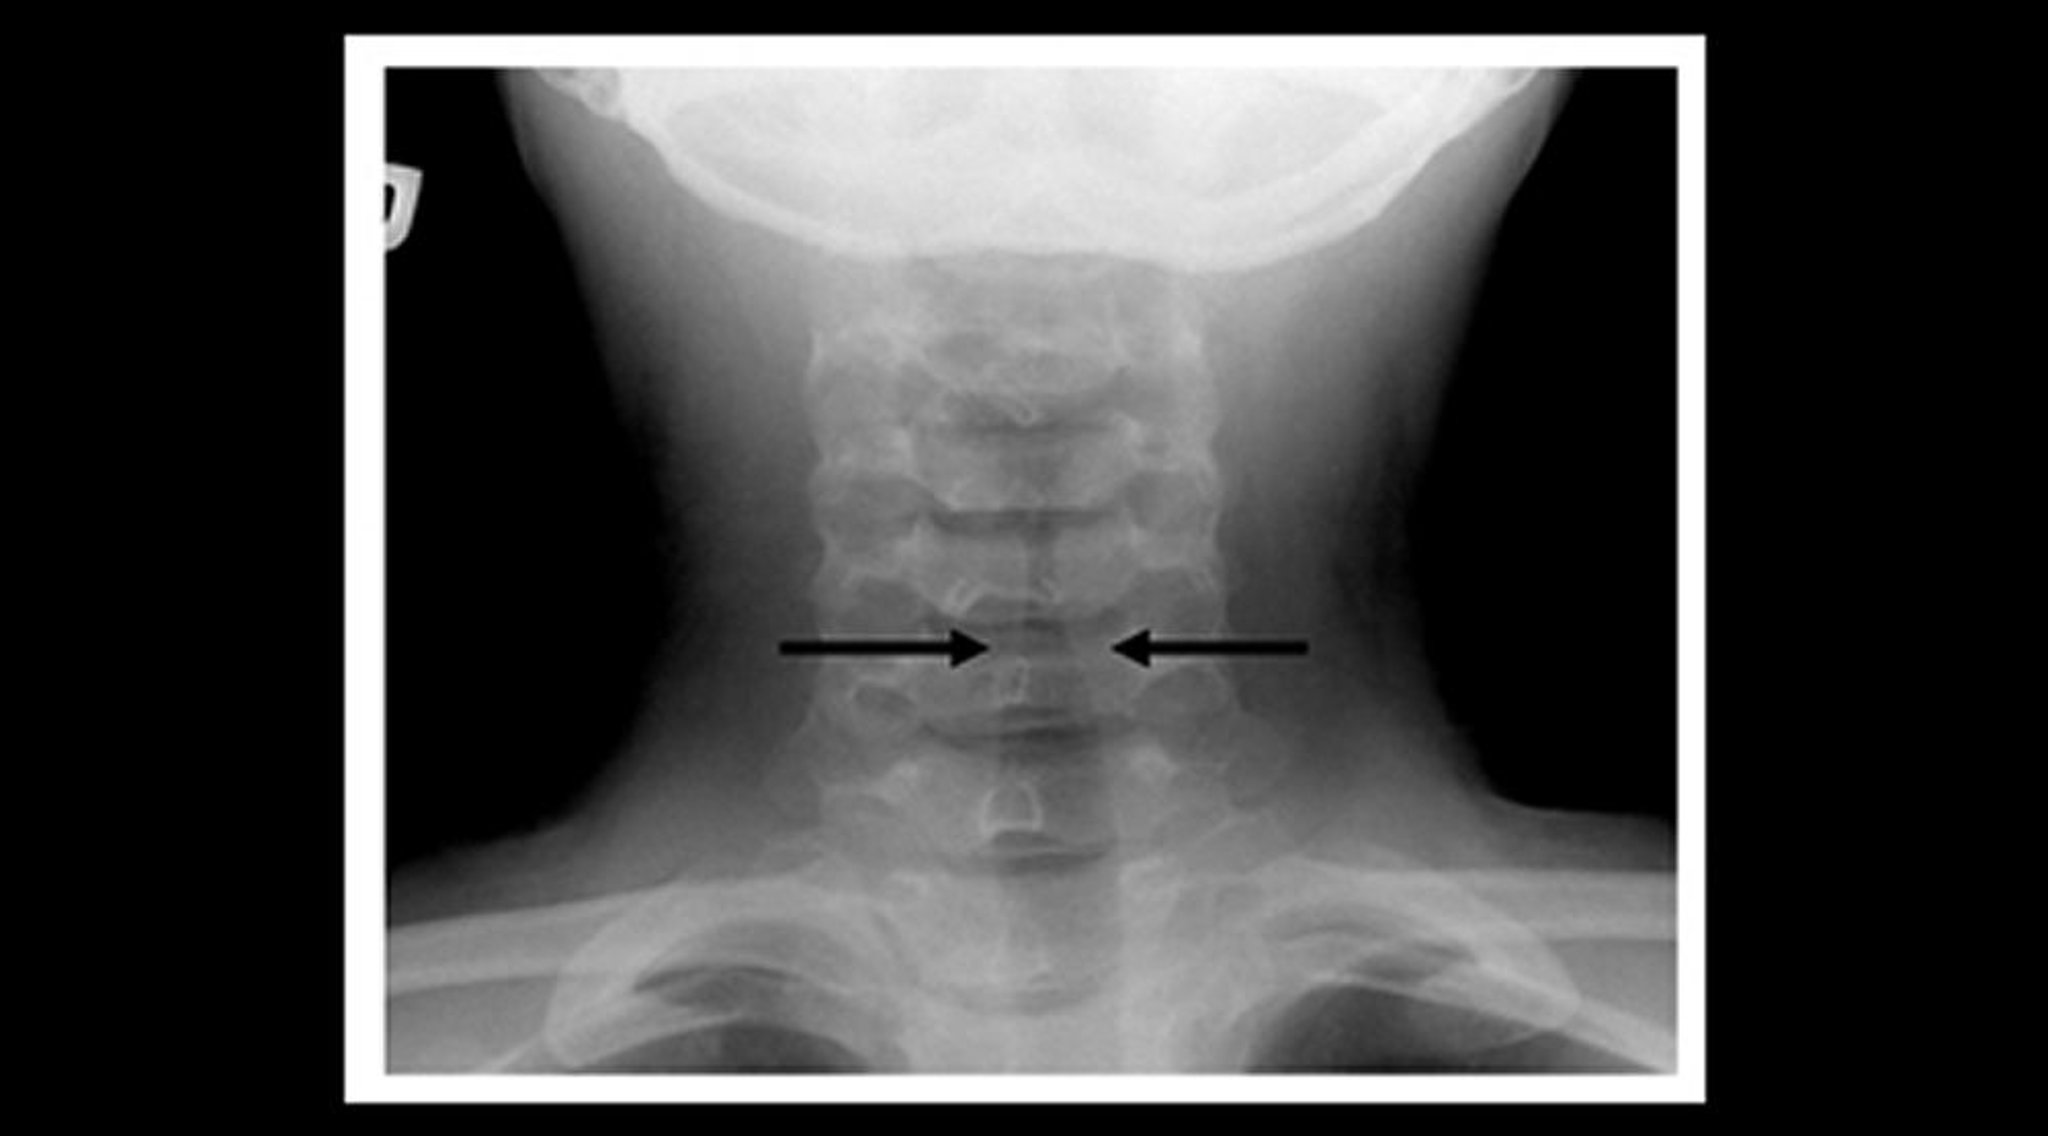

Radiografía de un niño con laringotraqueobronquitis espasmódica (crup) (cista coronal)

Radiografía de partes blandas del cuello de un niño con crup que muestra estrechamiento gradual de la sombra aérea traqueal subglótica (signo del campanario—flechas) y dilatación de los espacios aéreos faríngeos.